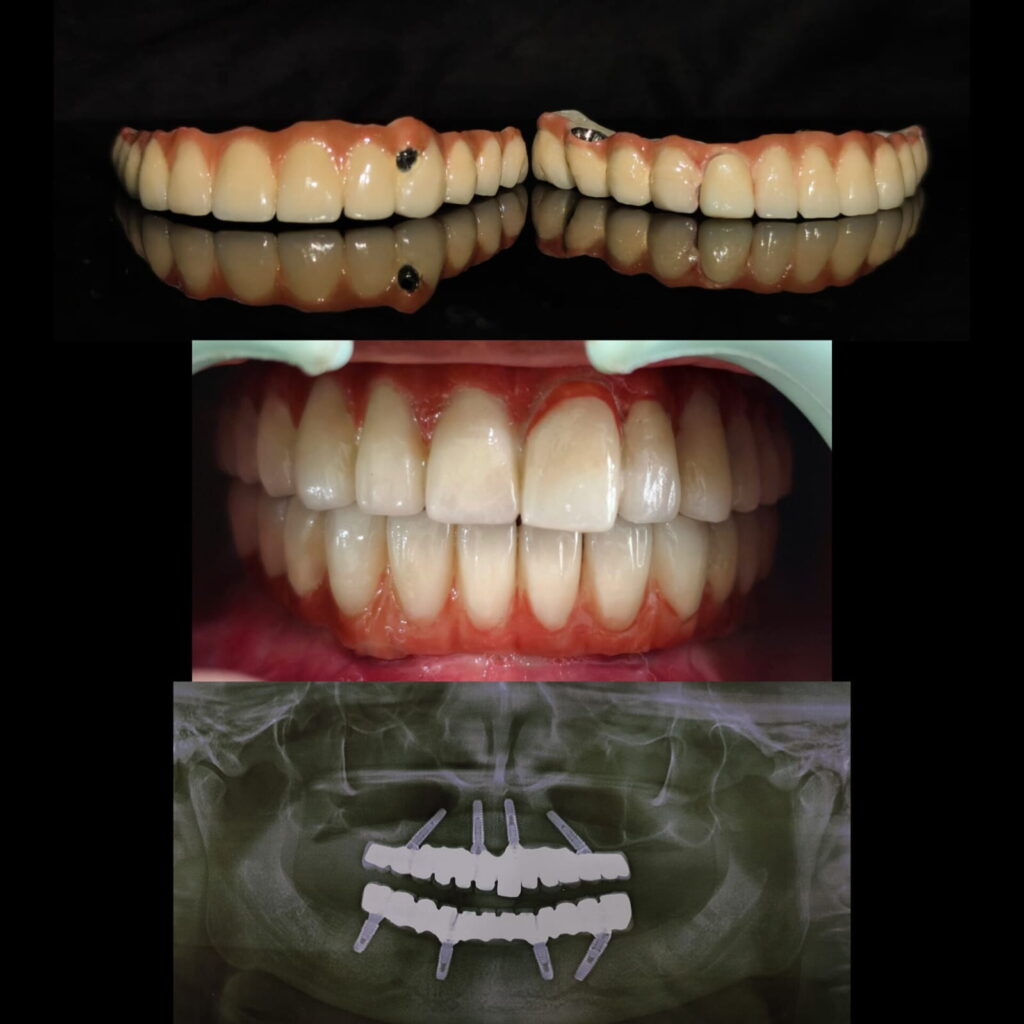

All on 4 full mouth rehabilitation case using Paulo malo guide